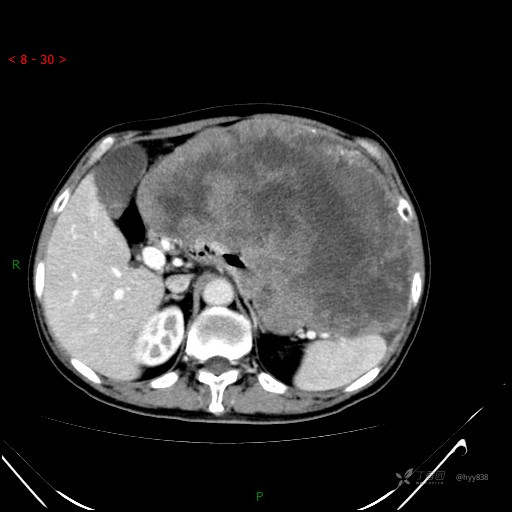

增强动脉期